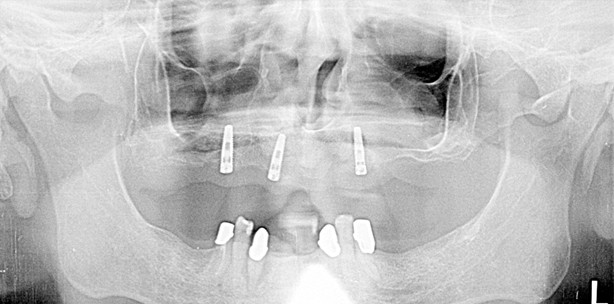

Im vorliegenden Fall war es dem Patienten von Bedeutung, eine langlebige, stabile Restauration zu bekommen, um endlich wieder kraftvoll zubeißen zu können. Die bisherige Totalprothese erfüllte nicht seine Ansprüche. Da wir wissen, dass bei Implantatarbeiten eine acht- bis zehnfache Kaukraft generiert wird und auch auf die Restauration einwirkt, müssen wir entsprechend planen. Um eine ausreichende Stabilität zu erreichen, wurden im Oberkiefer drei Implantate (Nobel ReplaceSelect 4.3 und 3.5; Nobel Biocare) inseriert (Abb. 1 und 2). Für die Einheilphase wurde die vorhandene Oberkieferprothese genutzt. Im Unterkiefer sollte die Kombinationsprothese im vollen Umfang erhalten bleiben, da die Pfeiler als unbedenklich eingestuft wurden und die Unterkieferprothese einen guten Halt und eine gute Passung hatte. Zwar hätte man die Unterkieferprothesen austauschen können, um eine noch bessere Verzahnung und Ästhetik zu erhalten, doch der Patient wollte ausschließlich eine neue Oberkieferrestauration und entschied sich gegen einen Austausch. In diesem Punkt muss man Verständnis zeigen und den Patienten in seiner Meinung respektieren. Bei der Restaurationsherstellung wurde das Backward Planning angewendet. Diese Vorgehensweise gehört bei Implantatarbeiten zum Laboralltag. Die Modellherstellung erfolgt mit einem hochwertigen Gips (Implantat-rock; picodent) und einer flexiblen, indirekt hergestellten Zahnfleischmaske (Majesthetik-Gingi-Implant; picodent), die dank ihrer Flexibilität eine präzise Kontrollmöglichkeit ist. Der erste Kontrollschritt des Meistermodells erfolgt per Kontrollschlüssel aus einer Kobaltchrom-Legierung (Wironit extrahart; Bego). Die Modellation des Kontrollschlüssels erweist sich als einfach und schnell. Mit einem längeren Wachsdraht (Durchmesser 3,5 mm), der um die Abformpfosten gelegt wird, formt man den Schlüssel, der anschließend im Speedguß-Verfahren gegossen wird. Diese sogenannte Metallbrezel und die Abformpfosten werden miteinander auf dem Modell durch einen lichthärtenden Kunststoff (picobello; picodent) verblockt (Abb. 3 und 4). Aufgrund der Divergenz der Implantate sollten die Abformpfosten, um ein leichtes Einsetzen zu ermöglichen, leicht angepasst werden. Dazu ist es ausreichend, den Drehschutz der Verbindungsnasen (tube in tube) zu beschleifen oder mit einem Poliergummi zu glätten (Abb. 5). Der Vorteil dieses Kontrollschlüssels liegt in seiner Stabilität und Genauigkeit. Mit dem Sheffield-Test kann so die Passung in situ sehr gut kontrolliert werden. Falls er dennoch nicht passt, weil die Abformung ungenau war, kann derselbe Schlüssel als Übertragungsschablone dienen. Somit wird das selektierte Implantat in situ neu verblockt und nach der Einprobe ins Modell repositioniert. Das im Meistermodell befindliche Modellanalog wird dafür vorher rausgefräst und stattdessen via Übertragungsschablone bzw. Kontrollschlüssel neu mit einem Autopolymerisat (z.B. Pattern Resin; GC) fixiert. Nach der erfolgreichen Einprobe und Kontrolle ist das Meistermodell präzise genug, sodass weitere Schritte folgen können.